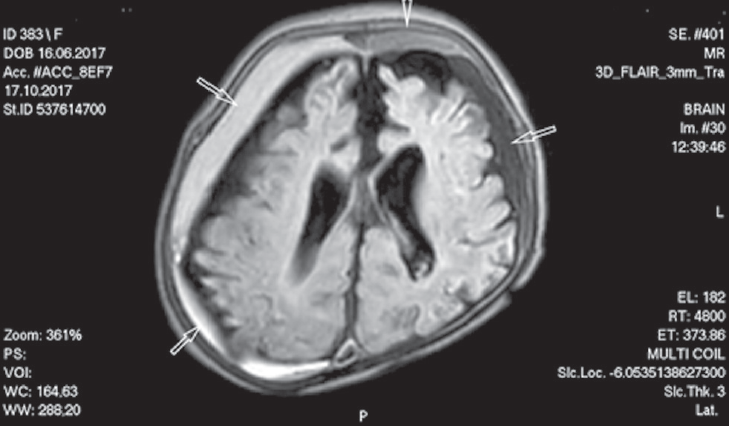

Пациентка 1 (новорожденная девочка), от третьих преждевременных оперативных родов на 33/34 неделе (отслойка плаценты), оценка по шкале Апгар 6/7 баллов, поступила на отделение реанимации и интенсивной терапии Перинатального центра СПбГПМУ на первый день жизни. У ребенка диагностирован врожденный порок развития — левосторонняя диафрагмальная грыжа, гипоплазия левого легкого, сопровождающиеся тяжелыми гемодинамическими нарушениями. Находилась на длительной инвазивной вентиляции легких. Приступы полифокальных клонических судорог выявлены на вторые сутки жизни. Пароксизмы купированы внутривенным введением Реланиума. Повторные эпизоды судорог (полиморфные, с преобладанием полифокальных миоклонических/клонических приступов) отмечены с 7-го дня жизни, назначена терапия Фенобарбиталом (стартовая доза 20 мг/кг в сутки), с четырехкратным суточным введением внутривенно Реланиума 0,5 % 0,2 мг/кг на один прием. В связи с продолжением и учащением приступов с 28-го дня жизни противосудорожная терапия усилена леветирацетамом/Кеппра (сироп по 20 мг/кг в сутки), на фоне приема которого приступы судорог стали менее продолжительными, но полиморфность приступов сохранялась. В неврологическом статусе отмечались церебральная депрессия с нарушением сознания (сомнолентность), диффузная мышечная гипотония, симметричное снижение глубоких рефлексов, отсутствие сосательного рефлекса. К концу первого месяца жизни появилась деформация костей по сагиттальному и лямбдовидному швам, отсутствовал прирост окружности головы (формировалась вторичная микроцефалия). Выполнен нейровизуализационный мониторинг. При проведении краниальной сонографии в неонатальном периоде выявлено патологическое увеличение субарахноидального пространства. К концу третьего месяца наблюдалось увеличение краниоцеребральной диспропорции (расширение подоболочечных пространств до 20 мм над лобными и теменными долями больших полушарий), расширение большой цистерны мозга. Учитывая выявление сонографических признаков расширения подоболочечных пространств, выполнена МРТ головного мозга в возрасте 3 месяцев 1 недели. На МРТ головного мозга были визуализированы двухсторонние субдуральные хронические гематомы с кровоизлияниями различной давности. Определялись атрофическое изменение белого и серого вещества обеих гемисфер, смешанная заместительная гидроцефалия. Данные представлены на рис. 1. После диагностирования субдуральных гематом было принято решение о проведении пациентке нейрохирургического вмешательства — выполнено наружное двухстороннее субдуральное дренирование под стереотаксической ультрасонографической навигацией. В послеоперационный период частота приступов и длительность уменьшились. Состояние оставалось крайне тяжелым, вспомогательная респираторная поддержка продолжалась. Отмечалось «малое сознание»: отсутствовала реакция на осмотр, ребенок открывал глаза спонтанно, без связи с раздражителем. Зрительной фиксации не получено. Черепная иннервация — зрачки нормотоничные, фотореакции сохранены, содружественного движения глазных яблок нет. Лицо симметричное. Язык по средней линии. Кашлевой рефлекс сохранен. Целенаправленной активности не выявлено. Обращали на себя внимание деформация костей мозговой части черепа, микроцефалия, частые стереотипии в дистальных отделах верхних конечностей в виде «вкручивания лампочек», на осмотре возникали гиперкинезы — тремор в конечностях среднеамплитудный, симметричный. Сохранялась диффузная мышечная гипотония. Выраженность глубоких рефлексов симметрично увеличилась.

Рис. 1. Магнитно-резонансная томограмма головного мозга. Стрелками отмечены хронические субдуральные гематомы различной давности. Атрофическое изменение белого и серого вещества обеих гемисфер, смешанная заместительная гидроцефалия. Режим 3D_Flair.

Fig. 1. Magnetic resonance imaging of the brain. Arrows indicate chronic subdural hematomas of various prescription. Atrophic change in the white and gray matter of both hemispheres, mixed replacement hydrocephalus. 3D_Flair mode